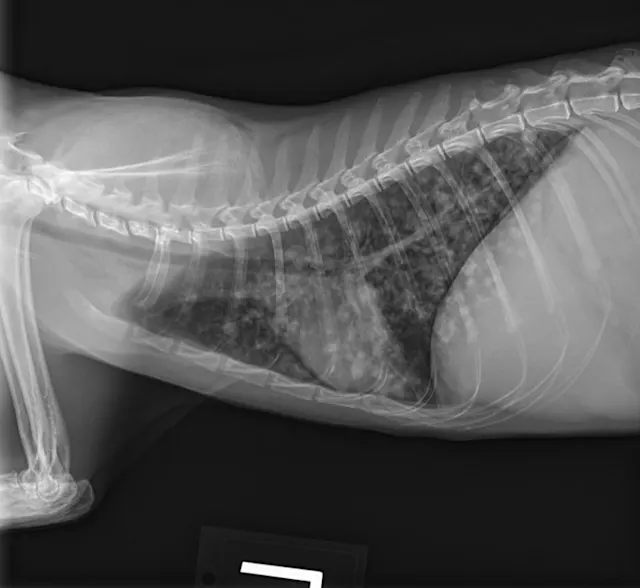

Butorphanol (0.2 mg/kg IV) was administered for sedation to obtain 3-view thoracic radiographs (left lateral, right lateral, ventrodorsal). Results revealed diffuse pulmonary nodular changes with an underlying bronchointerstitial pattern (Figure 1). Fungal pneumonia, parasitic pneumonia, neoplasia, and eosinophilic inflammatory disease were the most likely differentials for this pattern.

A

FIGURE 1 Left lateral (A), right lateral (B), and ventrodorsal (C) thoracic radiographs at the time of initial diagnosis. Diffuse pulmonary nodular changes with an underlying bronchointerstitial pattern can be seen.